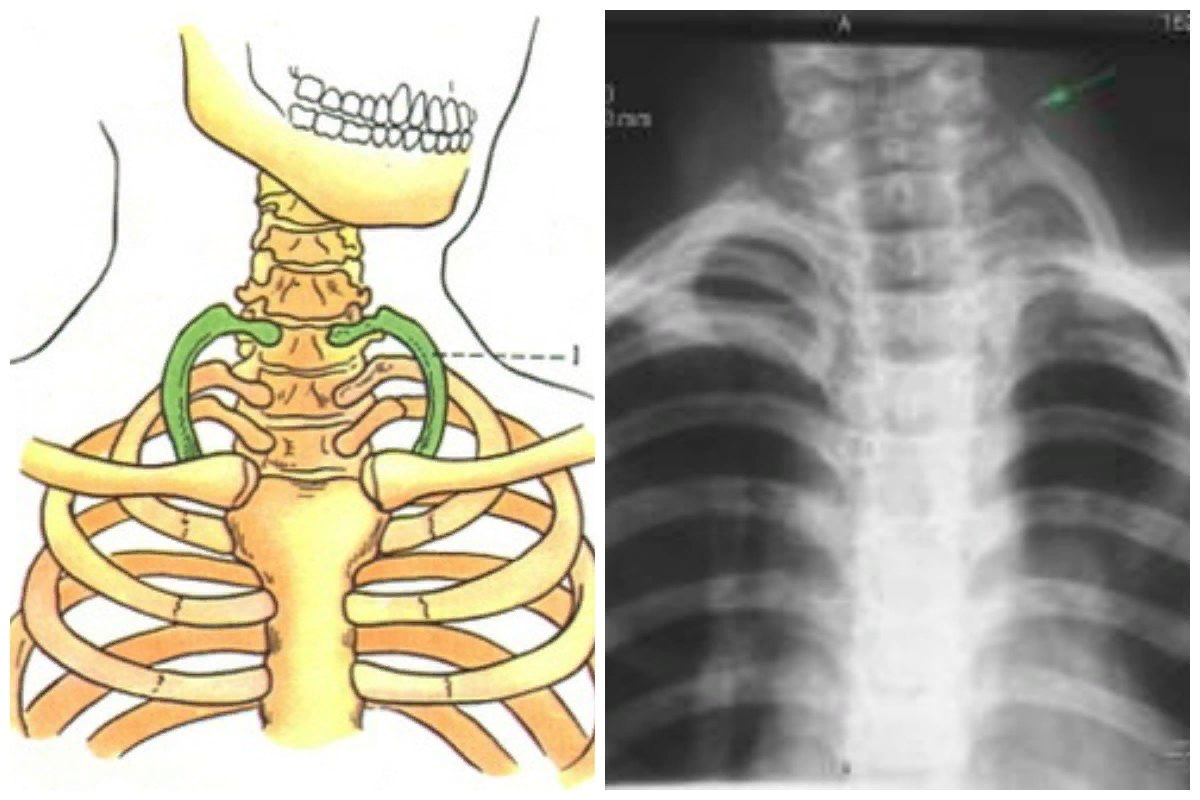

2. Шейные ребра

У некоторых людей есть 1-2 добавочных ребра сверху грудной клетки. В наши дни они есть лишь у 1% населения Земли. Скоро они вообще исчезнут.

10.13-я пара ребер

У наших ближайших родственников, шимпанзе и горилл, есть лишняя пара ребер. У большинства из нас их 12, но 8 % взрослых людей тоже имеют одну дополнительную.